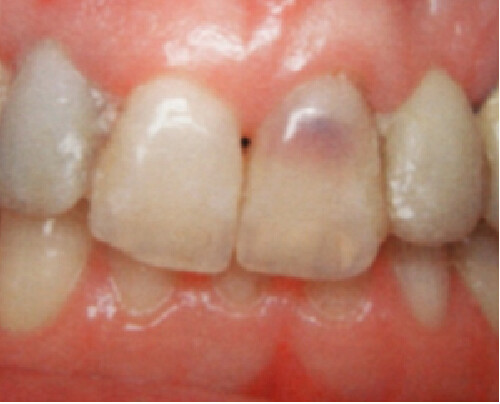

An internal resorption pink spot was historically referred to as the “pink tooth of Mummery,” named for the anatomist who described the condition. Like an ECR lesion, in this type of resorption, patients are typically asymptomatic, and the lesion is only noted either by its pink color that patients may notice prior to their visit or from routine radiographs.

If the lesion becomes significant in size, necrosis of the pulp usually occurs, at which point the patient will begin to have typical pulpitis-related symptoms. Since the vascular tissue becomes necrotic, the tooth’s color may appear darker or gray with discoloration. Root canal therapy will resolve this type of resorptive process. As long as the process has not resorbed a significant portion of the tooth, prognosis is favorable. Repairs can be made with bioceramics, even in situations where the lesion has perforated to the external surface.